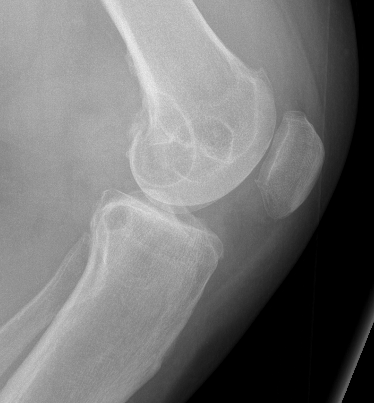

X-ray

Soft tissue swelling

Arthritic changes

Bone destruction

- invasion of adjacent metaphyseal cancellous bone

- may be suggestive of neoplasm

Bony involvement PVNS